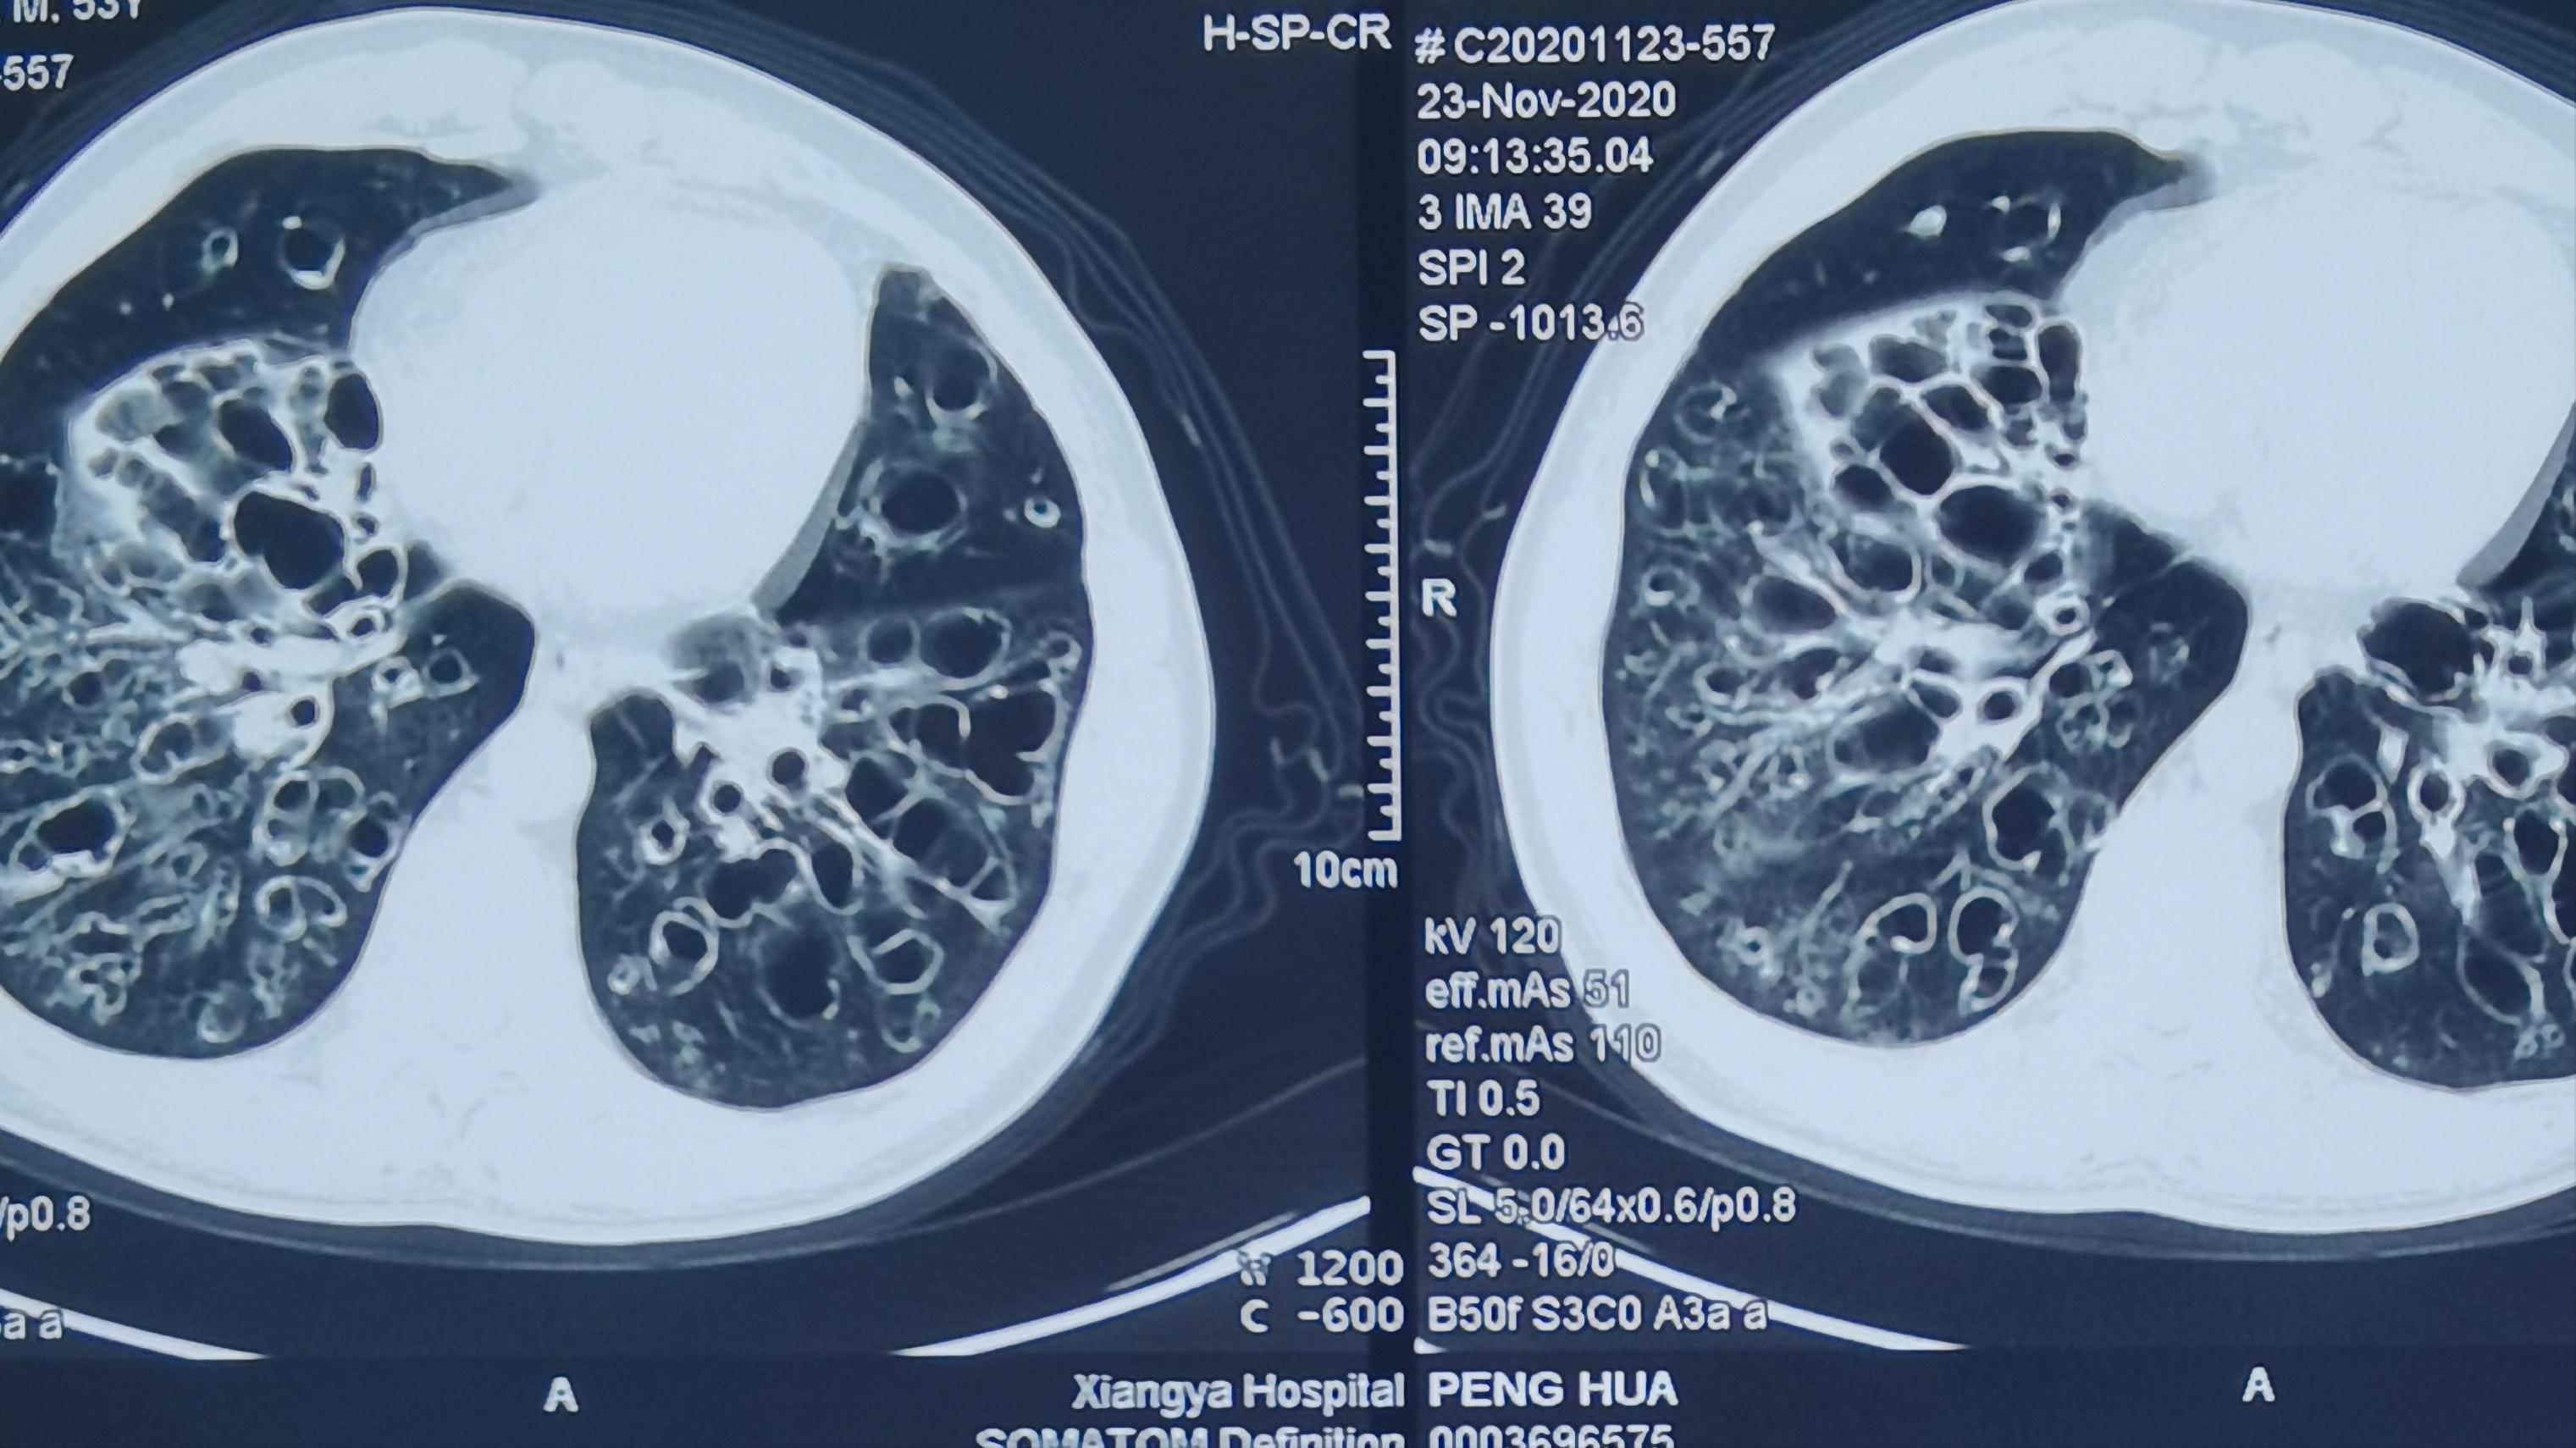

他用我的方法,坚持治疗了三个月痰液明显的减少,坚持治疗了6个月,感觉到呼吸困难也减轻了,痰液减少,每天就只有1~2口,有的时候可以完全没有黄痰,今天他来到病房里找我,复查了一个CT,CT中虽然他的支气管扩张非常的严重,但是里边的痰却几乎没有,说明他的痰已经基本上排出来了。